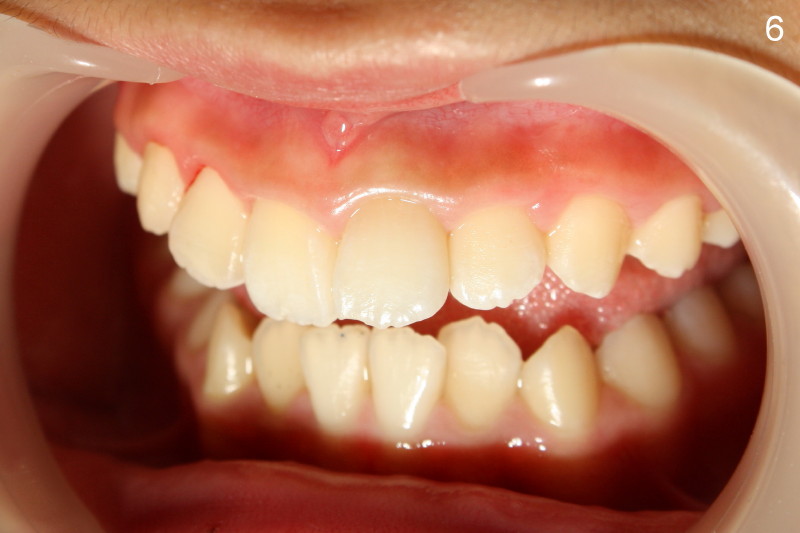

Discoloration of the tooth #9 is improved approximately 1 month of take home internal and external bleaching (Fig.5).  Fig.6 is a lateral view after brief in office bleaching (due to in-cooperation) and composite build up.